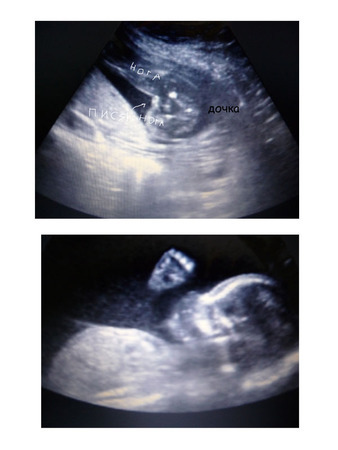

Но записана была к др врачу,а не к тому,что ходила в 12-14нед(добрая).Зато у этой(более строгая и ппротивная) в кабинете аппарат 3-4Д УЗИ.Порадовала меня показателями-все в норме,грит странно,почему плаценту в 21 нед на 3см посчитали низкой?что это норма.(Но я сравнила с результ снохи-мы на одном сроке с ней и в один день у одного и того ж доктора делали УЗИ)у нее 5 см было),так вот...сейчас у меня 4см.Но эт уже хорошо.Показала крупно писюльку)))Подтвердила что дееевочка)))Попросила ее фото сделать-прикиньте,150 р грит.Ну лан....отдала.Хотя на фото ну ниччче не понятно(((

Как непонятно, вон же на второй прям личико видно)) хорошая фотка! Хорошо, что купила)